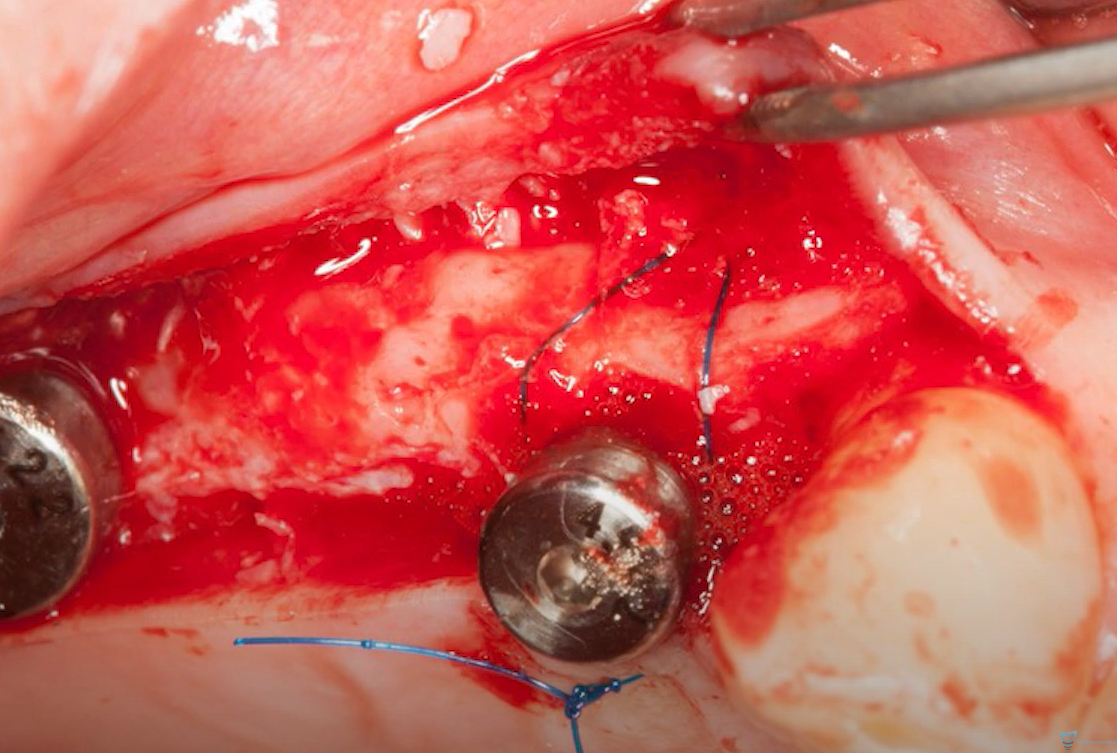

This is a manageable problem. A flap was raised, the periosteum was elevated, and an allograft-based bone graft was placed over the defect. This is a standard Steigmann technique. No membrane was required; the bone graft was contained by the periosteal flap, which was secured with a periosteal suture.

Bone defect closure using the Steigmann technique (periosteal envelope). Youtube/ Implantarium/ Rauf Aliyev